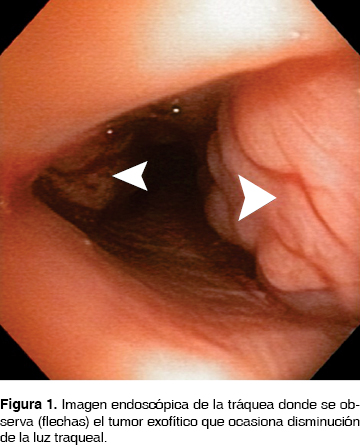

Su padecimiento actual lo inicio seis meses previos a su ingreso con disnea, estridor, con diagnóstico de asma por otra institución, tratada con broncodilatadores, esteroides, con mejoría parcial. La disnea progresó y el estridor en un inicio inspiratorio fue, posteriormente, bifásico con accesos de tos no productiva, con utilización de músculos accesorios para la ventilación. Ingresó al Servicio de Urgencias del Instituto Nacional de Enfermedades Respiratorias Ismael Cosío Villegas (INER), Ciudad de México, con datos de estenosis traqueal; motivo por el cual se le realizó broncoscopia flexible, observado tumor traqueal blanco nacarado, irregular (figura 1) desde el 2do. al 8vo. anillo traqueal (AT), 5 AT libres a la carina principal (CP) que ocasionaba disminución de la luz traqueal en un 90% y se dejó con intubación orotraqueal para permeabilizar la vía aérea. A los dos días le fue realizada una broncoscopia rígida con resección parcial de la tumoración para permeabilizar la vía aérea y toma de biopsia. En el posquirúrgico inmediato presentó enfisema subcutáneo en cuello, cara, tórax y neumotórax bilateral, colocándole sonda torácica bilateral. Por broncoscopia se identificó lesión traqueal, localizada en cara posterior en la unión con cara lateral de 1 cm de longitud a 3 cm de la CP, se dio manejo conservador con intubación orotraqueal ferulizando la lesión traqueal, con ventilación mecánica invasiva por siete días. El Servicio de Patología del INER reportó carcinoma adenoideo quístico. Para estadificarla se realizó TC de tórax (figura 2a, 2b), abdomen, pelvis y cráneo. Fue identificada la tumoración traqueal en tercio medio de la tráquea sin datos de lesiones a distancia. Se retiraron las sondas torácicas.